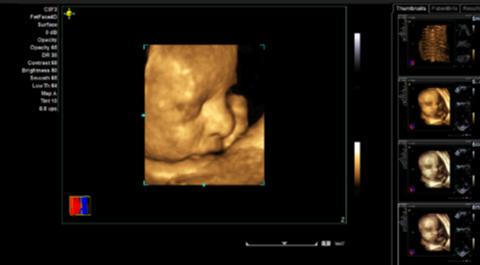

fourSight 4D 成像选件

- 提供了全面、实时的解剖结构和病理条件影像,可同时以所有空间尺寸显示高级 fourSight 4D 成像选件

- 提供 4D 成像高级功能